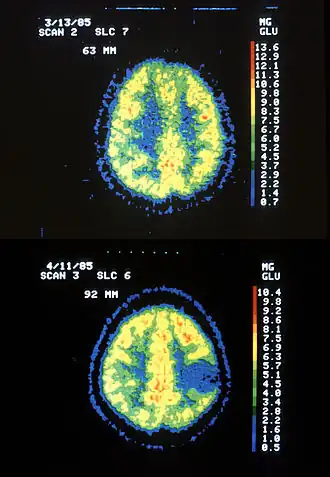

Generalmente se requiere una tomografía axial computarizada (TAC) o una resonancia magnética (IRM) para caracterizar el tumor y la extensión, incluyendo el tamaño, la ubicación y su consistencia. La TAC usualmente muestra distorsiones en los ventrículos tercero y lateral con desplazamiento de las arterias cerebrales anterior y media. El análisis histológico es requerido para estadificar el diagnóstico. Adicionalmente, se acostumbra realizar un examen médico completo, con el fin de verificar la integridad neurológica del individuo, incluidos visión, balance, coordinación y estado mental. Las biopsias de tumores cerebrales son procedimientos quirúrgicos dirigidos por un neurocirujano, las cuales son estadificadas dependiendo del tipo de células presentes, el grado de diferenciación y la cantidad de vasos sanguíneos.